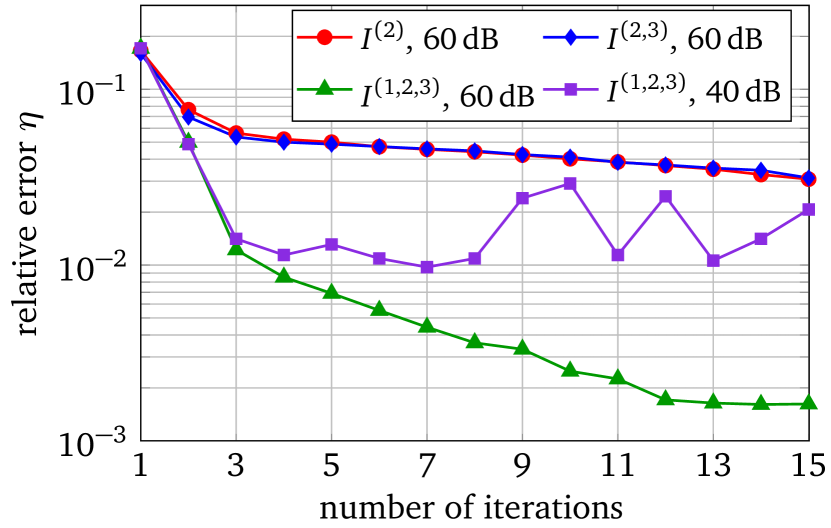

The LM-SCEM algorithm is used to reconstruct the distribution of . The initial guess is given as which is the value of the background tissue. The conductivity in the region for is supposed to be known. The values of are truncated to only update for with . The discontinuity caused by this truncation can be removed by applying (20) properly (either by mollification or simply by replacing the discontinuous values), but it does not cause any numerical problems since is small, so no special treatment was done in the following computation. The values of for the first 15 iterations are shown in Figure 4(a). The relative error is also given in Figure 4(b). With noise, the reconstruction with uniformly converges to with 15 iterations. The reconstructed is shown in Figure 5(a). To achieve a level of , it takes more than 40 iterations. A reconstruction with and is then carried out, but a similar speed of convergence and relative error is observed, result is in Figure 5(b). When the current pattern is further considered into the reconstruction, an obvious improvement of convergence is seen, and a relative error level is achieved with 14 iterations, the conductivity map is shown in Figure 5(c). Therefore, the convergence of LM-SCEM depends not only on the regularization parameter and the scaling parameter , but also on the current patterns for the measurements. Since indicates 0.1% of Gaussian noise in the simulated , the reconstructed result with is already good, and more iterations will not improve the result. To verify, a reconstruction with , and is carried out with (1% noise). Relative errors are shown in Figure 4(b), the reconstruction converges to within 7 iterations, and more iterations did not bring any improvements. The reconstructed result is given in Figure 5(d).